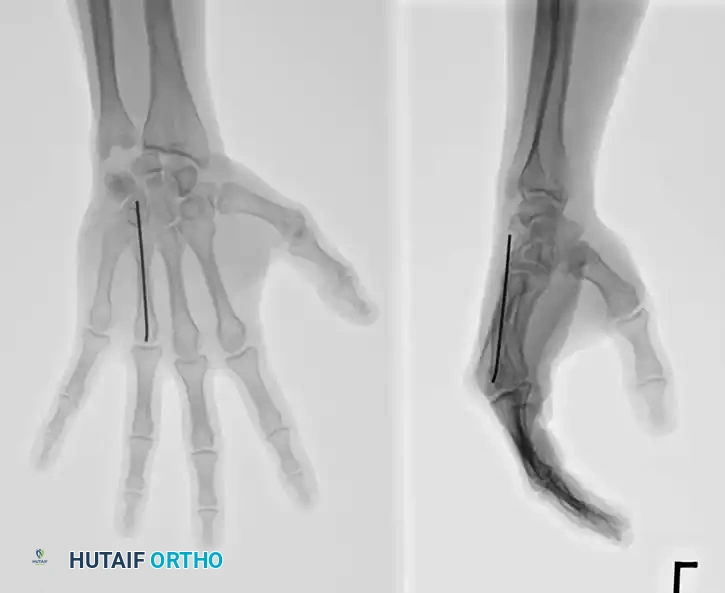

For transverse or short oblique fractures, intramedullary K-wire fixation provides excellent axial alignment with minimal soft-tissue stripping.

Technique: Introduce a 0.062-inch K-wire at the fracture site. Drill it retrograde out through the skin at the metacarpal base. While drilling, force a slight bow in the wire (convex toward the palm) and hold the wrist in flexion so the wire emerges safely on the dorsum of the wrist. Reduce the fracture anatomically. Drill the wire anterograde into the distal fragment, stopping just proximal to the articular surface of the MCP joint. Cut the proximal end beneath the skin.

Fig. 64-37 Radiograph showing reduction and fi xation of fracture of metacarpal shaft and neck.

Alternatively, closed percutaneous pinning can be performed. With the MCP joint acutely flexed (to tighten the collateral ligaments and control the distal fragment), introduce a K-wire through the metacarpal head and advance it across the fracture site under fluoroscopic guidance.